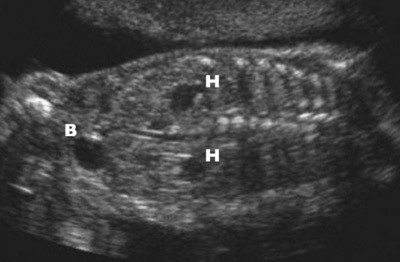

Misdannelsene ble diagnostisert prenatalt hos 160/389 (41 %). Denne andelen økte signifikant fra barn født i første tiårsperiode (35/148; 24 %) til sist fødte tiårskohort (125/241; 52 %) (p < 0,001). Figur 1 viser prevalensen av misdannelser fordelt på fire femårsperioder. Økningen skyldtes flere prenatalt diagnostiserte tilfeller av hydronefrose, henholdsvis 27 (0,4 per 1 000) og 96 (1,4 per 1 000) i de to tiårskohortene (p < 0,001). Tabell 1 viser årsakene til at nyre- og urinveismisdannelsene ble diagnostisert.

I denne populasjonsbaserte studien fant vi en prevalens for medfødte misdannelser i nyrer og urinveier på 2,7 per 1 000 levende fødte. I andre studier varierer funnene mellom 1,3 og 7,4 per 1 000 (1), (3–6). Det er betydelige forskjeller i inklusjonskriterier og inndeling av diagnoser i de forskjellige studiene. Dette er mest trolig forklaringen på forskjellene i prevalens, selv om en reell forskjell mellom studiepopulasjonene ikke kan utelukkes. Prevalensen steg betydelig (69 %) fra første til siste tiårskohort. Dette var først og fremst forårsaket av økt antall prenatalt diagnostiserte tilstander. For barn født i siste tiårsperiode ble hele 52 % av pasientene postnatalt utredet og diagnostisert på bakgrunn av patologiske forhold hos fosteret påvist ved ultralydscreening. De aller fleste av disse var hydronefroser som ikke trengte kirurgisk behandling (fig 2). Det har over tid både i Norge og andre land vært varierende og til dels uklare kriterier for diagnosen føtal hydronefrose (7–9).